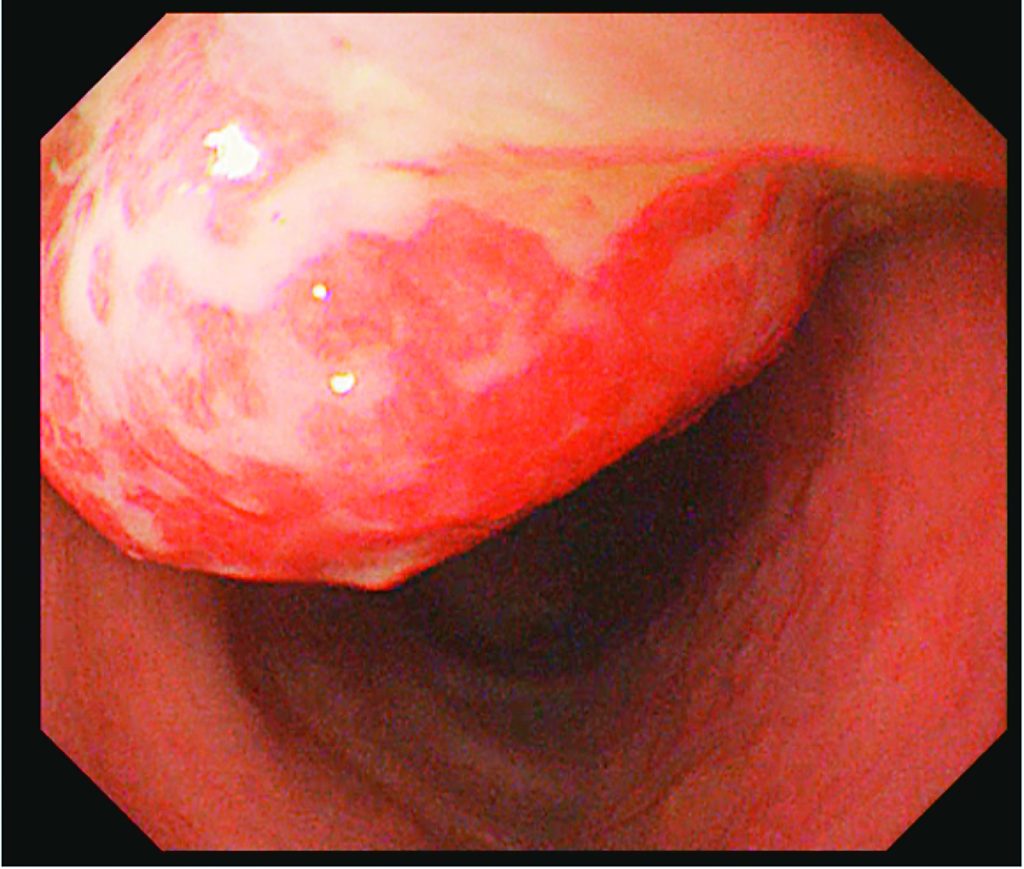

3歲林姓女童反覆出現間歇性血便,家長多次帶她就診並依便秘症狀治療,服用軟便藥後仍時好時壞。由於糞便潛血檢查呈陽性,經核子醫學掃描檢查排除為小腸處的梅克爾憩室,進行大腸鏡檢查發現有約2公分大的單顆息肉予以切除,術後病理報告顯示為良性的幼年型大腸息肉。治療後恢復良好,後續回診追蹤亦未再出現血便情形。

李致任表示,大部分的幼年型息肉可透過大腸鏡進行微創切除,在舒眠情況下將器械透過肛門進入大腸,並在影像系統的輔助下利用電圈套住息肉根部進行切除,再依情況決定是否需要使用止血夾加強止血;若息肉體積過大或經評估無法以大腸鏡完整切除,才需採外科手術處置。